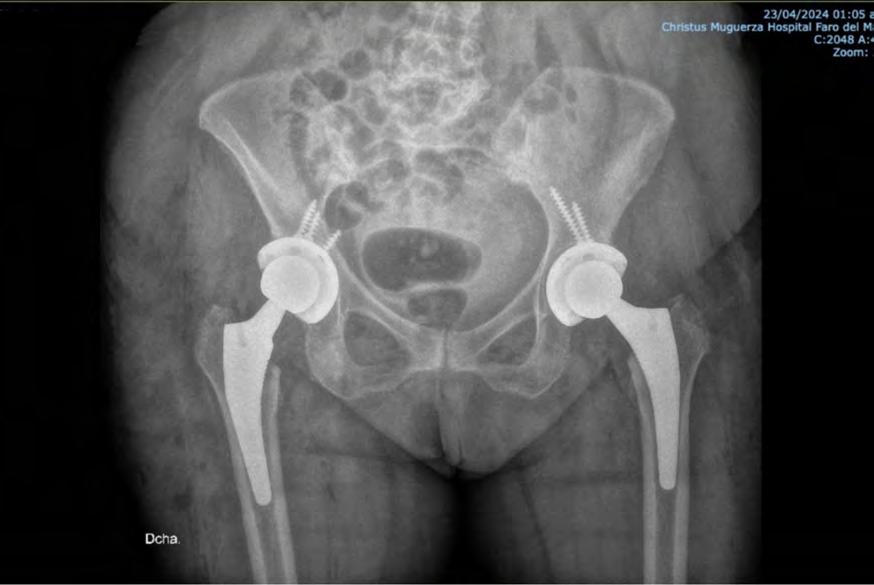

FRACTURA DE CADERA

Las fracturas de cadera son lesiones comunes y graves, para las personas de la tercera edad, actualmente consideramos un gran aumento en la frecuencia que esta se presenta, debido a tres factores: mayor índice de sobrevida, en consecuencia, más osteoporosis, peor estado nutricional y accidentes de mayor energía. Estas fracturas pueden tratarse mediante diferentes técnicasquirúrgicas:

PrótesisdeCadera:

-Sepuederealizarconosincemento

-Usadoenfracturasarticulares

-Deambulacióninmediata

-Riesgodeluxación

-Fracturaspordebajodelaprótesis

-Granniveldesangrado

En resumen, tanto el clavo centromedular como la prótesis de cadera son opciones para el tratamiento de fracturas de cadera. La elección depende de la situaciónclínica,laedaddelpacienteylapreferencia del cirujano. Es fundamental evaluar cada caso individualmente para determinar la mejor opción terapéutica.

GRUPO TRAUMATOLÓGICO DEL SURESTE

Ortopedia y Traumatología

Tel. 9999 21 49 09

Dr. Luis Manuel

Ochoa Gómez

Traumatología y Ortopedia

• Reemplazo Articular de Cadera